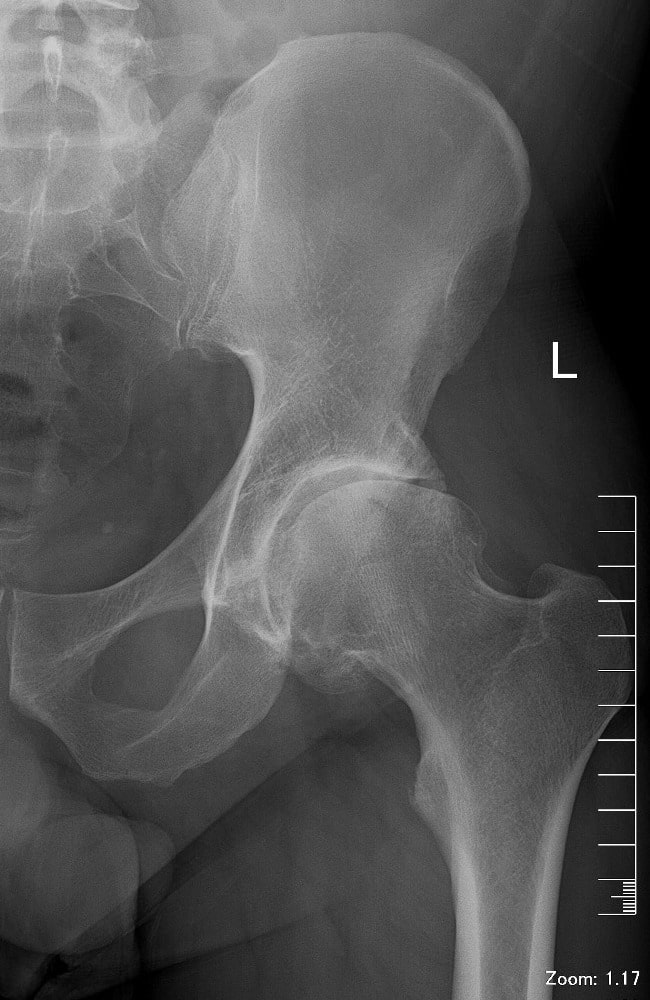

Снимок до эндопротезирования тазобедренного сустава Снимок после эндопротезирования тазобедренного сустава

Эндопротезирование тазобедренных суставов: фото до и после операции